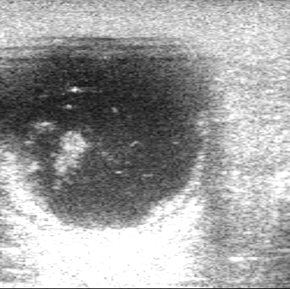

zwykle jeden jajnik znacznie powiększony, drugi nieaktywny (mieć na uwadze, że guzy mogą być obustronne)

wyższe prawdopodobieństwo u klaczy w wieku >10 lat, jednak możliwy w każdym wieku

> 30 pg/ml – podejrzenie ziarniszczaka lub przetrwałego pęcherzyka nieowulacyjnego

Zalety: rutynowe badanie, możliwość potwierdzenia subklinicznej aktywności pęcherzyków jajnikowych.

Ograniczenia: wynik badania należy rozpatrywać łącznie z obrazowaniem ultrasonograficznym.

Cel: diagnostyka ciąży od 80. dnia u klaczy i 120. dnia u oślicy. Wyniki uzyskane po 110. dniu ciąży są u klaczy najbardziej miarodajne i klinicznie użyteczne. Dodatkowo, dają informację o żywotności płodu i wydolności (stanie) łożyska.

Miejsce syntezy/ Rola fizjologiczna:

łożysko – powstaje na drodze syntezy z DHEA produkowanego w gonadach płodu, którego sekrecja znacząco zwiększa się pomiędzy 100. – 240. dniem ciąży, a następnie zaczyna spadać. Łożysko przekształca DHEA do estrogenów „ciążowych”, w dużej mierze siarczanu estronu

Kiedy oznaczamy:

podejrzenie/potwierdzenie wysokiej ciąży (od 80.dnia po owulacji)

pomocniczo: wątpliwości dotyczące żywotności płodu/wydolności łożyska

Interpretacja:

Między 80. a 100. dniem po zapłodnieniu wartości > 10 ng/ml wskazują na ciążę.

Po 100. dniu po zapłodnieniu wartości > 100 ng/ml wskazują na ciążę.

W przypadku ujemnego wyniku po 80. dniu ciąży, ciąża jest mało prawdopodobna (czułość testu 95–98%)

Przed podjęciem ważnych decyzji klinicznych zaleca się przeprowadzenie badania klinicznego.

Zalety: jeden z nielicznych parametrów laboratoryjnych pomocny w ocenie dobrostanu płodu i wydolności łożyska

Ograniczenia: dość długi czas oczekiwania. W przypadku oceny wydolności łożyska i żywotności płodu, gwałtowny, jednoznacznie diagnostyczny spadek stężenia E1S możliwy dopiero ok. 2 dni przed śmiercią płodu/poronieniem.